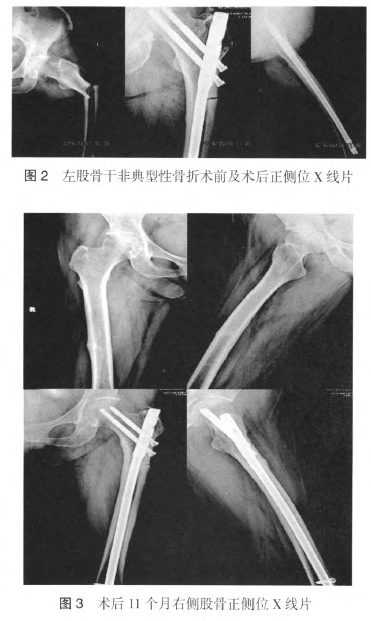

人院后,在全麻下行左侧股骨干骨折微创复位髓内钉内固定术,手术顺利(图2)。患者要求右侧骨折行保守治疗,拒绝手术。继续补充钙尔奇D,限制双侧下肢部分负重活动。定期复查X线片,术后11个月右侧股骨干没有发生骨折移位,左侧股骨干骨折周径3/4骨皮质连续性恢复,外侧皮质仍可见骨折间隙(图3)。